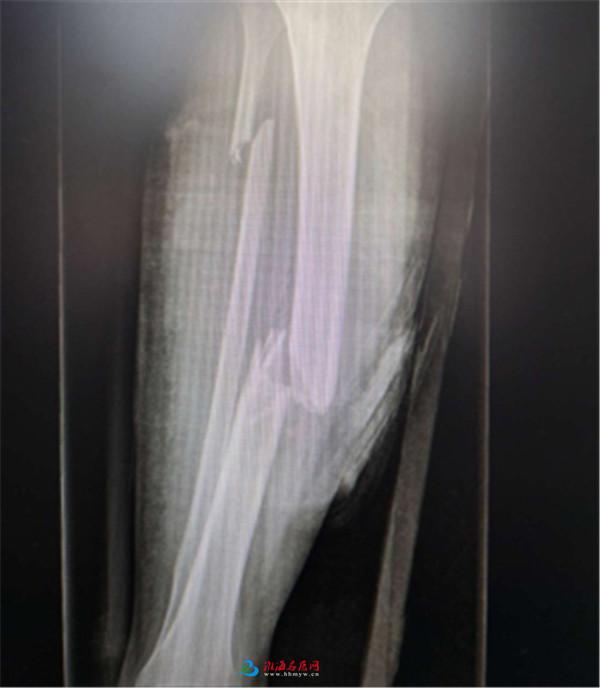

术前X片

这是一位津巴布韦在矿业大学学习的留学生,在驾驶摩托过程中不慎发生车祸,致其右侧胫腓骨开放性骨折,全身多发软组织挫裂伤,到医院时已处于失血性休克状态。

该院创伤骨科接收后,根据病情立即启动创伤MDT,对其进行补液扩容、清创覆盖伤口,同时联系医院总值班,迅速开通绿色救护通道。医护人员一边对其头部、胸部、腹部CT及双下肢作X线检查,一边电话联系住院处办理住院手续,做好术前准备,化验室加急化验结果并紧急备血。由于而时值盛夏,医院血库备存紧张,但如果不能及时持续输血,病人极可能会出现生命危险,为此,该院血液科紧急实施优先输血方案,保证病人供血充足。